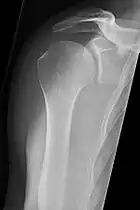

_X-ray_of_a_normal_shoulder.jpg.webp)

These include:

- AP-projection 40° posterior oblique after Grashey

The body has to be rotated about 30 to 45 degrees towards the shoulder to be imaged, and the standing or sitting patient lets the arm hang. This method reveals the joint gap and the vertical alignment towards the socket.[17]

- Transaxillary projection

The arm should be abducted 80 to 100 degrees. This method reveals:[17]

- The horizontal alignment of the humerus head in respect to the socket, and the lateral clavicle in respect to the acromion.

- Lesions of the anterior and posterior socket border or of the tuberculum minus.

- The eventual non-closure of the acromial apophysis.

- The coraco-humeral interval

- Y-projection

The lateral contour of the shoulder should be positioned in front of the film in a way that the longitudinal axis of the scapula continues parallel to the path of the rays. This method reveals:[17]

- The horizontal centralization of the humerus head and socket.

- The osseous margins of the coraco-acromial arch and hence the supraspinatus outlet canal.

- The shape of the acromion

This projection has a low tolerance for errors and accordingly needs proper execution.[17] The Y-projection can be traced back to Wijnblath’s 1933 published cavitas-en-face projection.[18]

In the UK, the standard projections of the shoulder are AP and Lateral Scapula or Axillary Projection.[15]